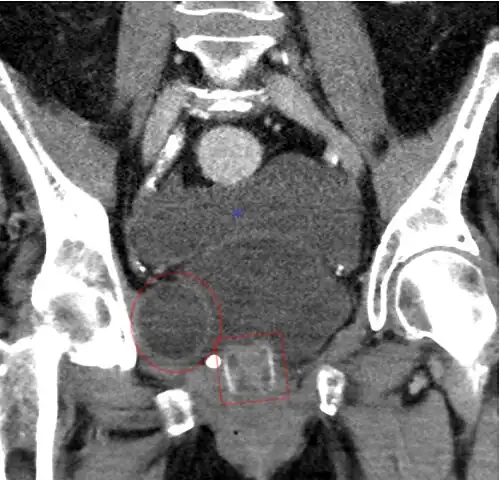

An X-ray image of implanted ZSI 375. The device is deactivated – the spring is compressed below the top of the cylinder. Patient is incontinent. -